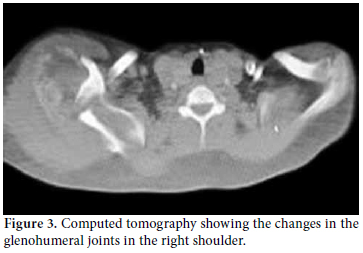

Radiological examinations showed destruction in the joints and bone structure of the affected right shoulder, elbow, and wrist as well as soft tissue calcification (Figure 2). Upper extremity computed tomography (CT) also indicated that the bilateral glenohumeral joint relations were disturbed. The joint on the right was dislocated, and both humeral heads were destructed and fragmented, with the damage more visible on the right side. Furthermore, extensive soft tissue calcification was noted in the neighborhood of the joints together with destructive changes in the glenoid fossa and proximal humeral metaphysis. Additionally, the lesions that showed bilaterally similar but moderately asymmetric involvement were evaluated with regard to neuropathic arthropathy (Figure 3).

In the scintigraphic examination, we found increased activity involvement in both shoulders, especially in the right shoulder as well as on the right humeral head and in the distal phalanx of the finger. Both the scintigraphic and the radiological findings were compatible with secondary degenerative changes, especially in the benign bone pathologies (Figure 4). Furthermore, craniocervical magnetic resonance imaging (MRI) (especially FLAIR sequence) found cerebellar tonsillar herniation compatible with the Chiari type I malformation in the accompanying syrinx cavity in the cervical spinal cord (Figure 5). In addition, the arterial/venous Doppler ultrasonography (USG) results for both the lower and upper extremities were normal.